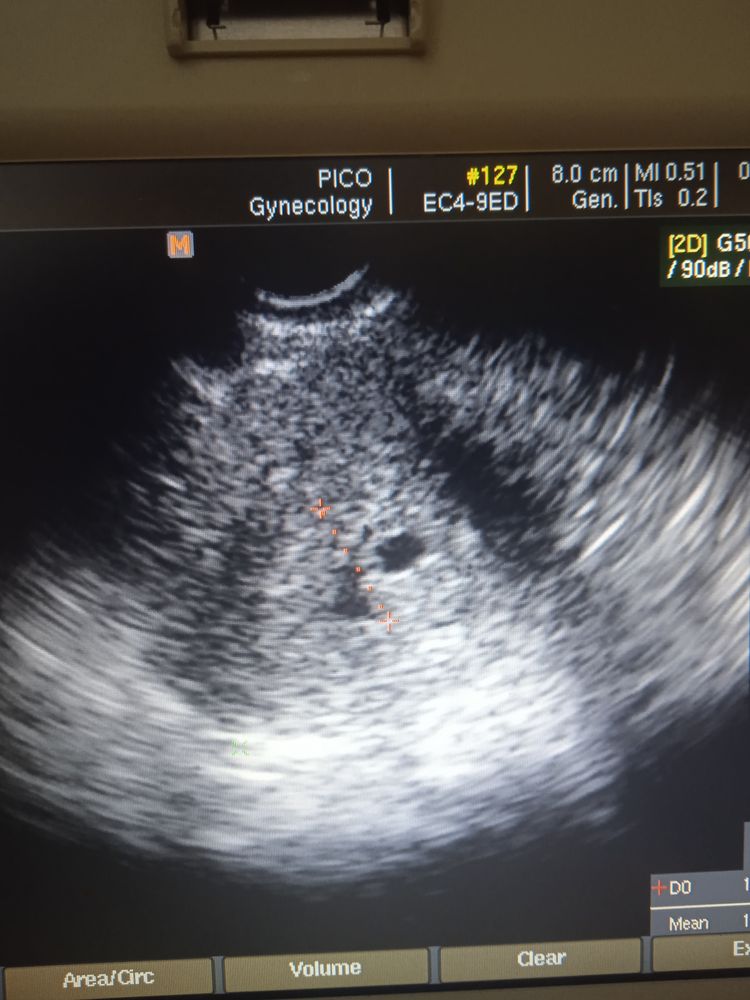

Если я правильно считаю, у вас 39 дпп, хгч для такого срока низкий. Уже д.б не только ПЯ, но и эмбрион и СБ. Если этого нет, то увы.

К сожалению очень маленький хгч для такого срока,маленькое пя без эмбриона и сб…

К сожалению,скоре всего нет. На такому сроке у вас должен был быть уже и эмбрион,и сб. А не просто плодное яйцо. И хгч мал. Замершая, скорее всего.

Изображение Изображение

Ekaterina , ХГЧ высокий не для этого срока, плодное яйцо без эмбриона. И сильное кровотечение. Сегодня наконец-то после результата ХГЧ мне поставят капельницу.